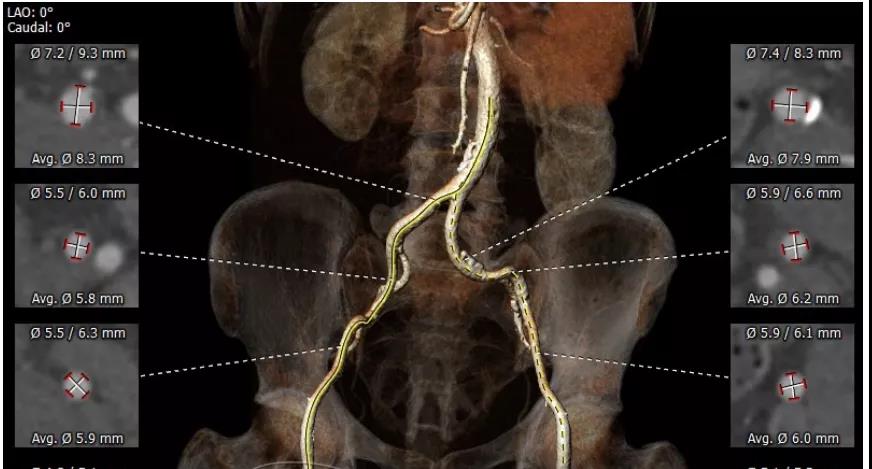

CT重建显示患者双侧髂动脉、股动脉、锁骨下动脉质量极差,多发钙化狭窄伴局部夹层,无法经股动脉和锁骨下动脉入路。而且患者重度肺气肿致心脏两侧受压,心尖被压缩在胸骨及肋弓骨性融合后方,亦无法经心尖入路。评估双侧颈动脉近端均有钙化斑块伴轻度狭窄,平均管径约6mm,左侧管径略大于右侧。颅内Willis环交通支通畅,可以耐受经单侧颈动脉介入手术。

髂动脉、股动脉状况极差

颈动脉评估